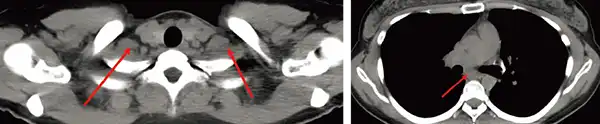

同症例の4年経過後のCTです。

腫瘍は消失しています。このように、従来は放射線治療が困難であった症例も、放射線治療で治すことができるようになってきました。

全ての症例に根治的治療が行えるようになった訳ではありませんが、技術や装置の進歩により根治的放射線治療を行うことができる幅が広がってきました。